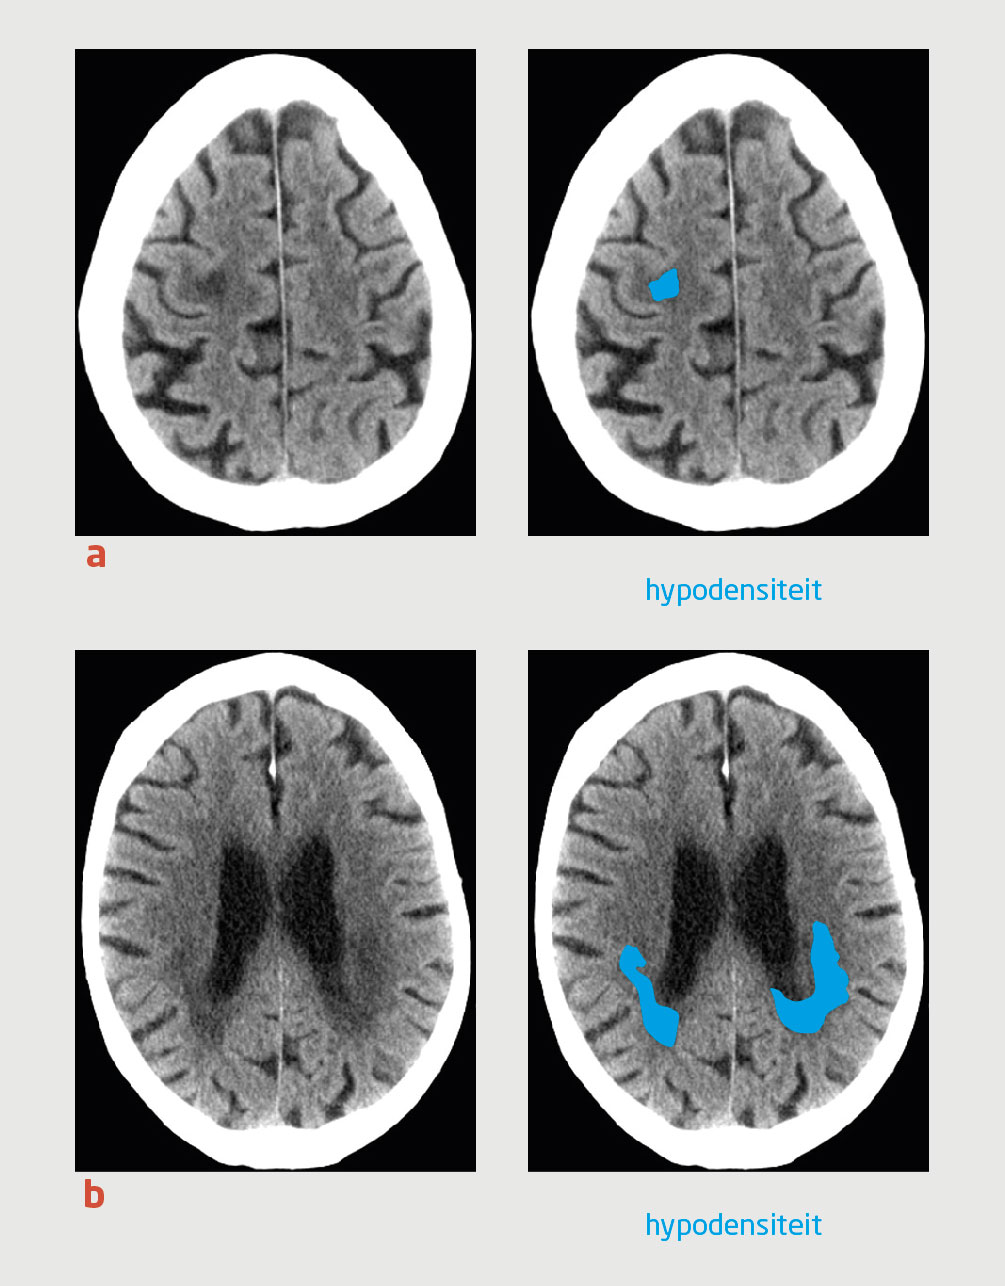

2 maanden later namen wij patiënt op vanwege toenemend krachtverlies in de linker lichaamshelft. Een CT-scan van de hersenen toonde een toename van het hypodense gebied rechts frontopariëtaal, zonder betrokkenheid van de cortex. Een aanvullende MRI-scan van de hersenen liet geen diffusierestrictie zien (figuur 2). Het laboratoriumonderzoek toonde geen aanwijzingen voor progressie van de CLL. Differentiaaldiagnostisch dachten wij aan PML of een glioom.

Figuur 2 |

MRI-scans van de hersenen van een 79-jarige man, waarop een afwijkend gebied in de subcorticale witte stof rechts frontopariëtaal is te zien met (a) een hyperintens signaal op de T2-gewogen opname, (b) een verhoogd signaal aan de periferie op de diffusie-gewogen B1000-opname en (c) een hypo-intens signaal op de T1-gewogen opname, zonder aankleuring na toediening van gadolinium.

Bij patiënten met neurologische uitvalsverschijnselen zal meestal in eerste instantie een CT-scan van de hersenen verricht worden. Bij patiënten met PML kunnen op de scan een of meerdere hypodensiteiten in de witte stof zichtbaar zijn, waarbij de cortex vrijwel gespaard blijft. In retrospect waren zulke hypodensiteiten ook zichtbaar op de eerste CT-scan van onze patiënt (zie figuur 1a). Er waren echter ook afwijkingen te zien die goed bij ischemische schade kunnen passen (zie figuur 1b). Op een MRI-scan zijn de wittestofafwijkingen bij PML te zien als een hyperintens signaal op de T2-gewogen opname en de FLAIR-opname en als een hypo-intens signaal op de T1-gewogen opname. Deze afwijkingen hebben geen massawerking en kleuren normaliter niet aan na toediening van gadolinium (zie figuur 2). Geïsoleerde wittestofafwijkingen op een CT- of MRI-scan maken cerebrale ischemie onwaarschijnlijker. Omdat de afwijkingen niet aankleuren na toediening van contrast, is een maligniteit eveneens onwaarschijnlijk.